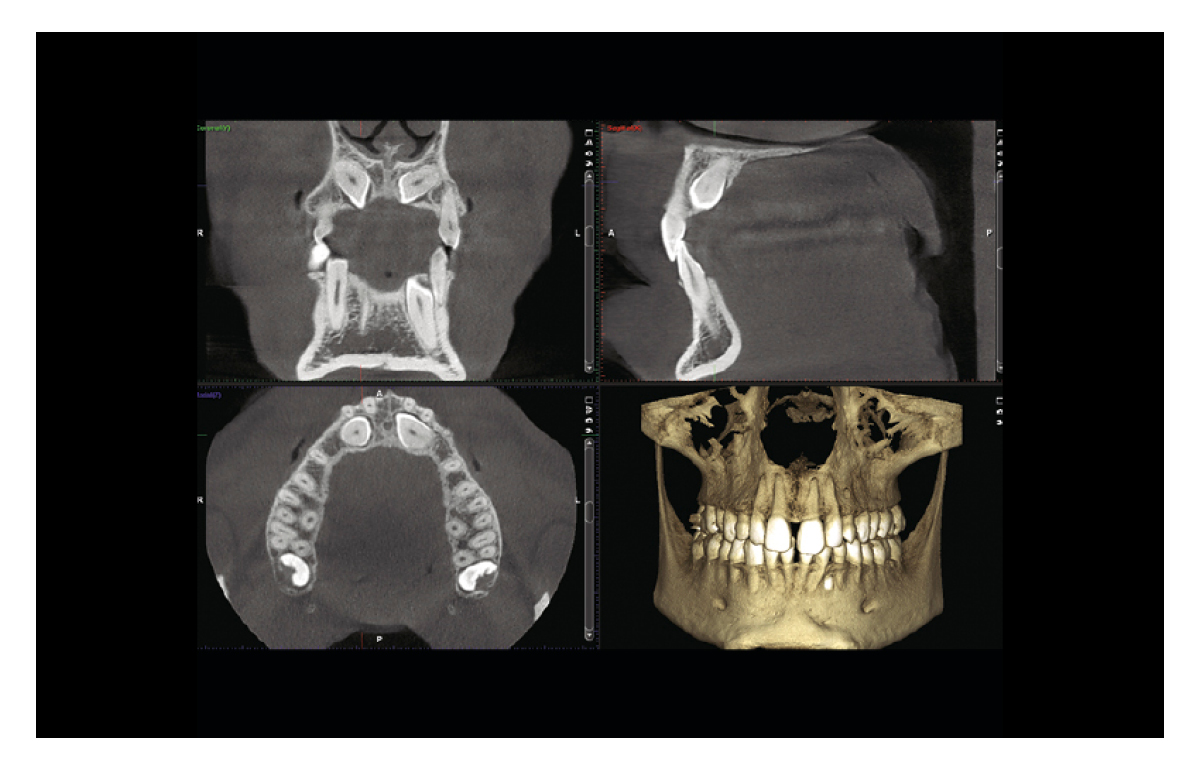

Premium image quality

Packed with intelligent high-tech solutions and algorithms, all Planmeca CBCT units offer an effortless imaging process and crystal-clear images — and at a low dose. These units have been designed to prevent human error with options for correcting movement as well as noise and artefact reduction.

Automatic patient movement correction

As the first end-user solution for patient movement correction in the industry, the Planmeca CALM™ algorithm not only saves clinicians time, but also guards patients from unnecessary exposures. It works with all volume and voxel sizes and adds less than 30 seconds to the overall reconstruction time.

Comprehensive imaging software

Planmeca Romexis® is the leading software platform for dentistry. It provides a rich set of tools to meet the imaging requirements set by any dental facility – from a small clinic to a large hospital. The software supports all 2D and 3D dental imaging as well as CAD/CAM workflows with its extensive range of tools.